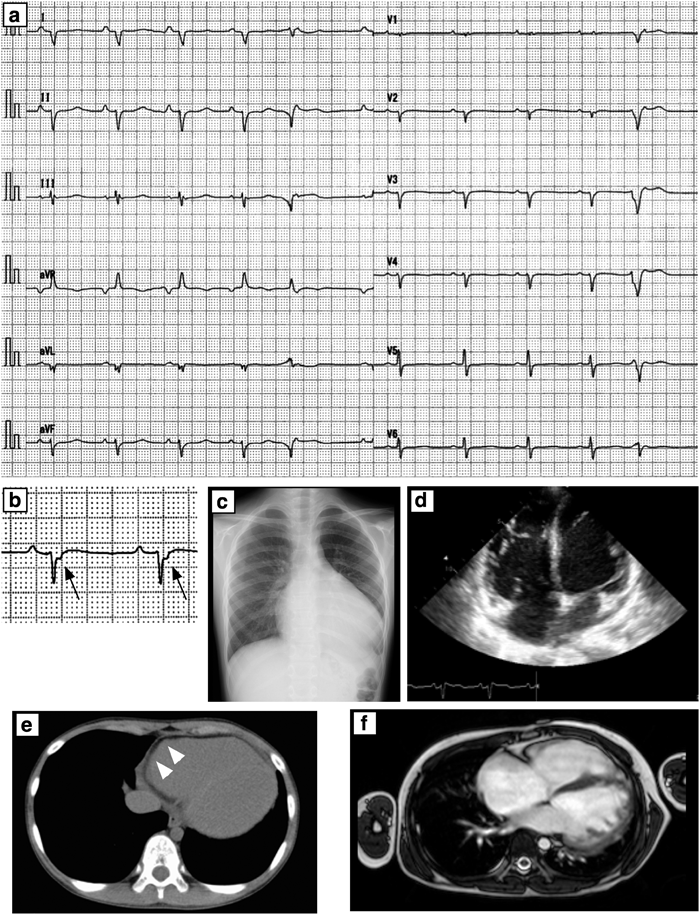

12誘導心電図ではQRS軸が不定軸で低電位,V1–3誘導においてはイプシロン波を認めた(Fig. 2a, b).血液検査ではBNP 895.1 pg/mLと高値を認めたが,その他の血液生化学所見には異常を認めなかった.Holter心電図では右室起源の多源性心室期外収縮と13連発のnon-sustained VTを認めた.遅延電位ではfQRS 173 ms(>114 ms),RMS40 3.0 µV(<20 µV),LAS 88.5 ms(>38 ms)と異常を認めた.胸部単純X線では心拡大を認めた(CTR 67%)(Fig. 2c)心エコーでは両心室の著明な拡大,左室収縮能の著明な低下(LVFS 0.04)と軽度の僧帽弁逆流を認めた(Fig. 2.d).心肺運動負荷試験では最大酸素摂取量15.4 mL/kg/min(予測値の38%),無酸素性作業閾値10.3 mL/kg/min(予測値の26%)と機能低下を認めた.マルチスライスCTでは右室壁の脂肪変性を認めた(Fig. 2e).心臓MRIでは両心室で内腔の拡大と駆出率の低下(右室駆出率23%,右室拡張末期容積237 mL,左室駆出率17%,左室拡張末期容積179 mL)を認めた(Fig. 2f).

Fig. 2 ECG and diagnostic imaging at admission

a: Twelve leads ECG showed sinus rhythm, north-west axis and PVC. b: Epsilon wave was found in V2 (arrow). c: Chest X-ray showed moderate cardiomegaly without lung congestion. d: Biventricular dilatation was noted with echocardiogram (apical four chamber view). e: multi-detector CT showed fatty change in the right ventricle (arrow head). f: Cardiac MRI revealed significant biventricular dilatation and reduced contraction. Fibro-fatty replacement was not prominent on this MRI image.